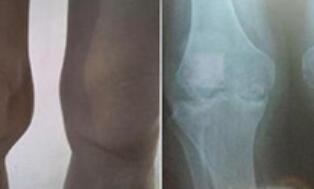

入院后,王怀庆主任马上为小吴安排了检查,症状:手关节肿胀、疼痛,早上有6分钟晨僵,膝关节肿胀,下蹲困难,行走时疼痛。X光检查结果:双膝关节未见脱位,关节间隙狭窄,关节面光滑,关节囊肿胀。化验:AS...[详细]

王怀庆主任为刘先生做了详细的检查。在经过认真查体后发现,刘先生双手指远端指间关节海伯登结节,关节僵硬,握拳无力。双膝肿胀Ⅲ°,皮温高,浮髌试验(+),屈100°伸-20°。...[详细]